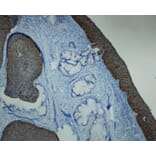

Cervical lymph node metastasis of oropharyngeal HPV-associated squamous cell carcinoma stained with Anti-p16 Antibody (A8237). Shows strong and specific positive immunostaining of dysplastic and neoplastic epithelium, with no reactivity in normal epithelial and stromal structures. Formalin fixed, paraffin embedded human tissues (4µm sections) stained.